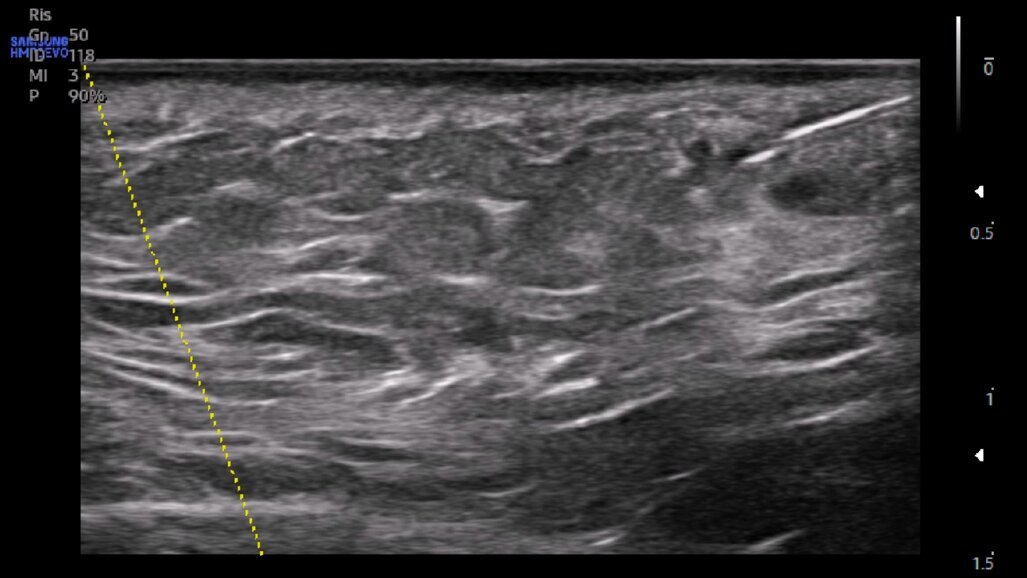

Gli ultrasuoni forniscono immagini in tempo reale con accuratezza variabile e dipendente dalle capacità dell’operatore e dalle potenzialità dell’apparecchiatura ecografica per uno studio accurato della cute e degli strati più superficiali del volto ma nascosti dall’epidermide (Fig. 1). Consentono una mappatura precisa delle strutture vascolari a prescindere dalle loro varianti anatomiche ed una valutazione della motilità dei piani muscolari. Ciò significa che con l’esame ecografico è possibile passare dall’osservazione anatomica statica a quella dinamica e valutare le straordinarie differenze ai fini diagnostici, esecutivi e post-operatori (Fig. 2) (clicca QUI e guarda il video). A causa della crescente popolarità delle procedure estetiche mininvasive al volto mediante tecniche iniettive/infiltrative/implantari, l’esame ecografico facciale è diventato fondamentale per tracciare i prodotti iniettabili, prevenire complicanze e, se necessario, riconoscerle per intervenire tempestivamente. Eventi avversi possono verificarsi al momento dell’iniezione, come le occlusioni o le compressioni vascolari, subito dopo il trattamento, come le infezioni, o diversi mesi dopo, come la comparsa di reazioni nodulari infiammatorie. Eseguire una metodica estetica al volto, sia essa infiltrazione di filler, iniezione intramuscolare di tossina botulinica o impianto di fili di trazione o di biostimolazione, sotto guida ecografica, fornisce un riscontro dinamico contestuale del posizionamento del riempitivo, consentendo al clinico di operare nell’area anatomica prescelta evitando sconfinamenti indesiderati (clicca QUI e guarda il video).

L’incidenza di complicanze vascolari dopo le iniezioni di filler pare essere 1/6600 (0,015%). Tuttavia, sebbene questo rischio non sembri molto elevato, anche un operatore esperto può incorrere in questo evento avverso. Se, da un lato, gli ultrasuoni possono aiutare nell’identificare e valutare il decorso dei vasi sanguigni a rischio di occlusione o compressione (Fig. 3), dall’altro, in caso di evento avverso correlato al filler a base di acido ialuronico, l’enzima ialuronidasi può essere iniettato con la guida degli ultrasuoni esattamente nel deposito del prodotto per una sua mirata dissoluzione (Fig. 4). Con l’avanzare dell’età, l’immagine della cute si modifica sia negli spessori sia nel numero degli annessi. L’esame ecografico contribuisce a visualizzare il progressivo deterioramento cutaneo: un assottigliamento del derma, la riduzione delle fibre collagene, la degenerazione delle fibre di elastina e la disidratazione influiscono sull’ecogenicità dei tessuti esaminati (Fig. 5).

Fig. 1

Fig. 2

Fig. 3

Fig. 4

Fig. 5